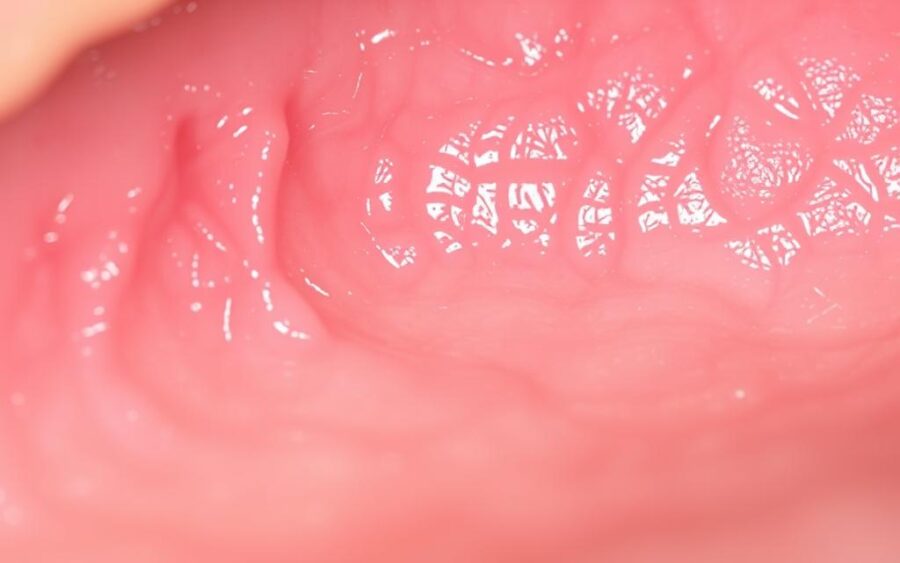

Błona śluzowa to warstwa komórkowa pokrywająca powierzchnie wewnętrzne ust i gardła. Jej budowa składa się z warstwy śluzowej, gęstej tkanki podskórnej oraz naczyń krwionośnych. Szybka regeneracja komórek sprawia, że odnawia się co tydzień, co utrzymuje jej wydolność.

Objawy chorób błony śluzowej

Wczesne rozpoznawanie objawów chorób błony śluzowej jamy ustnej ułatwia skuteczną diagnostykę chorób błony śluzowej jamy ustnej. Cechy charakterystyczne wskazują na potrzebę konkretnych badań. Najczęściej występujące oznaki wymagają uwagi i szybkiej reakcji.

Zmiany kolorystyczne

Niezbędne jest ścisłe śledzenie zmian w wyglądzie powierzchni. Poniżej przedstawiono kluczowe oznaki:

| Kolor | Opis | Możliwe przyczyny |

|---|---|---|

| Czerwony | Nadpobudliwość naczyniowa | Zapalenie, alergie |

| Biały | Plamy na powierzchni | Kandydoza, uszkodzenia |

Czerwone plamy i owrzodzenia

Różowe lub rdzawe plamki oznaczają ewidentne uszkodzenia. Owrzodzenia często towarzyszą infekcjom bakteryjnym lub grzybiczym. Zwróć uwagę na: